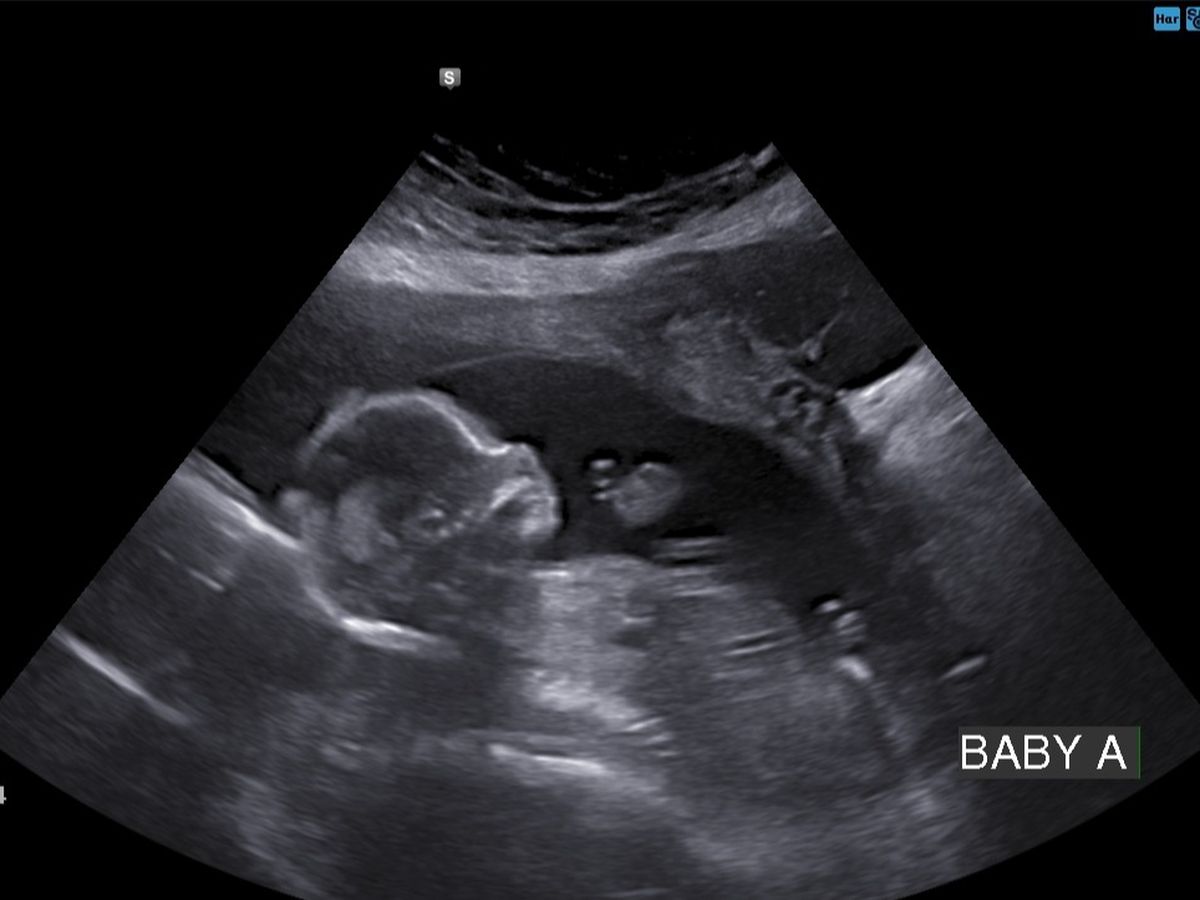

Brittany was recently diagnosed with Sjögren's Syndrome and hospitalized for the past week due to complications with baby A and her heart. Baby A has a complete heart block, with fluid around the heart and abdomen and does not have a good prognosis. Brittany will have to continue infusions, as well as numerous appointments 2+ times a week to monitor baby A's current condition with possible extensive medical travel in the future as things progress.